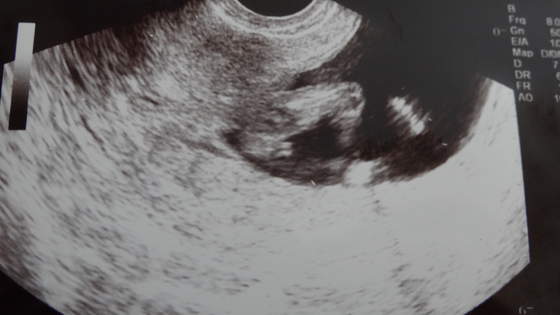

No i zerkamy na płeć (of kors nic nie mówiłam, że tydzień temu byłam gdzie indziej i lekarka sugerowała, że to mógłby być chłopiec). A gin mówi, że na 95% dziewczynka

No i rzeczywiście, już żadnego cypelka nie widać!!! A podobieństwo tego obrazu do tego jak dowiedzieliśmy się w I ciąży, że będzie dziewczynka uderzające!!! Wow, ale byłoby super! Szczególnie, że marzyliśmy o drugiej dziewczynce.